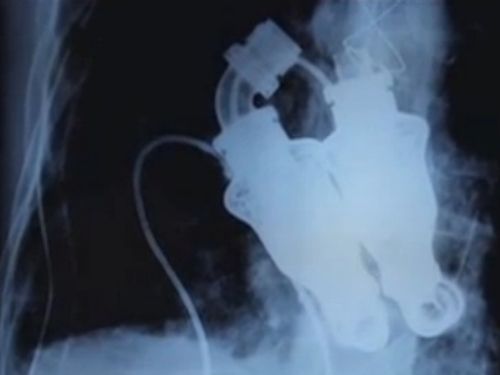

Turbinas podem substituir coração humano

Foi-se o tempo em que você precisava das batidas do seu coração para viver. Numa cirurgia inovadora realizada no ano passado, os médicos William Cohn e Bud Frazierd, do Instituto do Coração no Texas, em Houston, substituíram o coração de um homem que estava falhando por duas turbinas, resultando na primeira pessoa a viver sem pulso, mostra reportagem publicada no site “New Scientist”.

Comparado a corações artificiais que imitam os de verdade, os médicos acreditam que o dispositivo é mais durável, já que não tem membranas flexíveis ou complexos mecanismos de torção.

- Ninguém foi capaz de criar um dispositivo capaz de durar dois anos ou mais e que não se desgasta tão rápido - diz Cohn.

O aparelho ainda não é aprovado para uso, mas Cohn diz que os cientistas estão desenvolvendo um protocolo de estudo para que eles tentem usá-lo de novo. Embora Craig Lewis, o paciente de 55 anos, tenha morrido cinco semanas depois, isso aconteceu devido a uma doença subjacente e os médicos afirmaram que o dispositivo estava funcionando perfeitamente.

Apesar de a tecnologia poder ser usada para replicar as funções do coração, os pesquisadores também estão tentando criar um coração novo, do zero. Em casos onde o órgão não está tão danificado, também é possível consertá-lo com o estímulo certo.